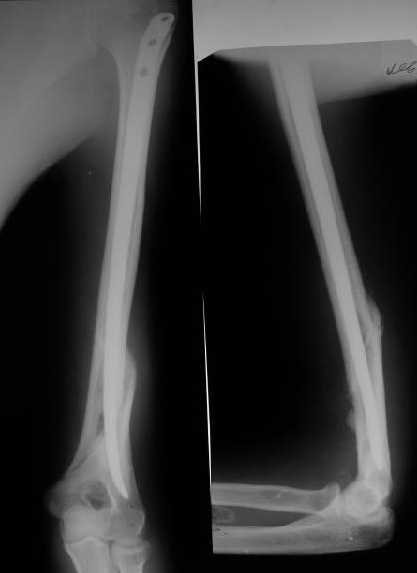

Снимки до, через 1 и 2 мес. после синтеза.